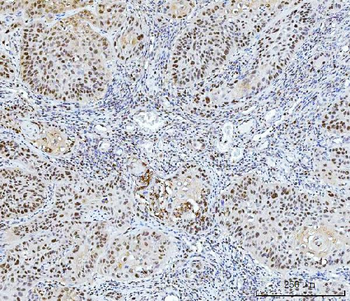

![Anti-FEN1 [SAIC-21C-4]](/images//pub/media/catalog/product/NewWebsite/35/orb1089994_1.png)

![Anti-FEN1 [SAIC-21C-4]](/images/pub/media/catalog/product/NewWebsite/35/orb1089994_2.png)

![Anti-FEN1 [SAIC-21C-4]](/images/pub/media/catalog/product/NewWebsite/35/orb1089994_3.png)